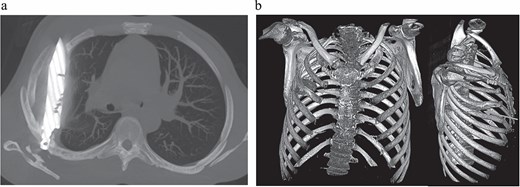

Initial imaging with a lateral chest radiograph demonstrated a retained metallic object in the mid-thorax, with surrounding opacification likely representing a resolving or chronic loculated hematoma or post-traumatic fibrosis, a sequela of the patient's stab wound (Fig. 2). Subsequent computed tomography (CT) imaging (Fig. 3a and b) revealed a retained foreign metallic object traversing the right chest. The entry point was identified through the right scapula, between the 5th and 6th posterior intercostal spaces, with the tip extending to the 3rd and 4th anterior intercostal spaces. CT also demonstrated healed fractures of the right scapula, 5th and 6th ribs posteriorly, and the 3rd rib anteriorly. An elliptical area of consolidation with central hypodensity was observed, further supporting the interpretation of a resolved or chronic loculated hematoma. The remainder of the lung parenchyma appeared unremarkable.

Lateral chest radiograph demonstrating a retained metallic object (knife) in the mid-thorax with surrounding opacification consistent with post-traumatic fibrosis following a stab wound.

(a) CT chest maximum intensity projection (MIP) demonstrating a retained metallic foreign body (knife) traversing the right chest, with associated healed fractures. (b) 3D reconstructed CT chest image demonstrating the retained knife and associated skeletal injuries.